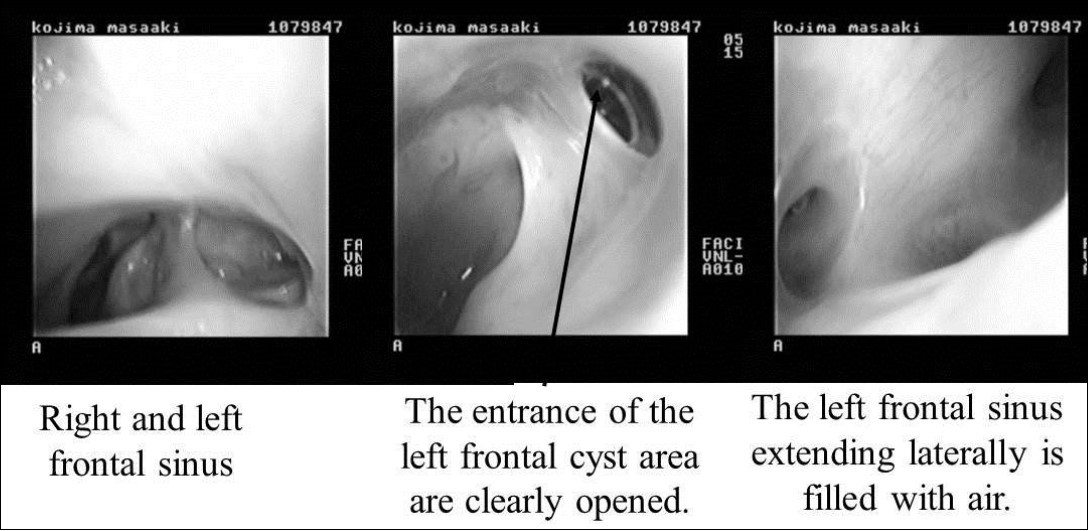

On April 16, 2008, reoperation was performed to place a ceramic implant, but some pus was found in the left lateral sinus. The lesion was debrided, the dead space was filled with muscle, and surgery was completed without ceramic implantation. On October 17, 2008, another surgery confirmed that the frontal sinus was clean, and a ceramic implant was placed. The postoperative course has been good, and as of May 2009, the frontal sinus extending laterally is filled with air (Figure 5, Figure 6).

Figure 6.Endoscopic findings after surgery. Right and left frontal sinuses. The entrance of the left frontal cyst area is clearly opened (black arrow). The left frontal sinus extending laterally is filled with air.